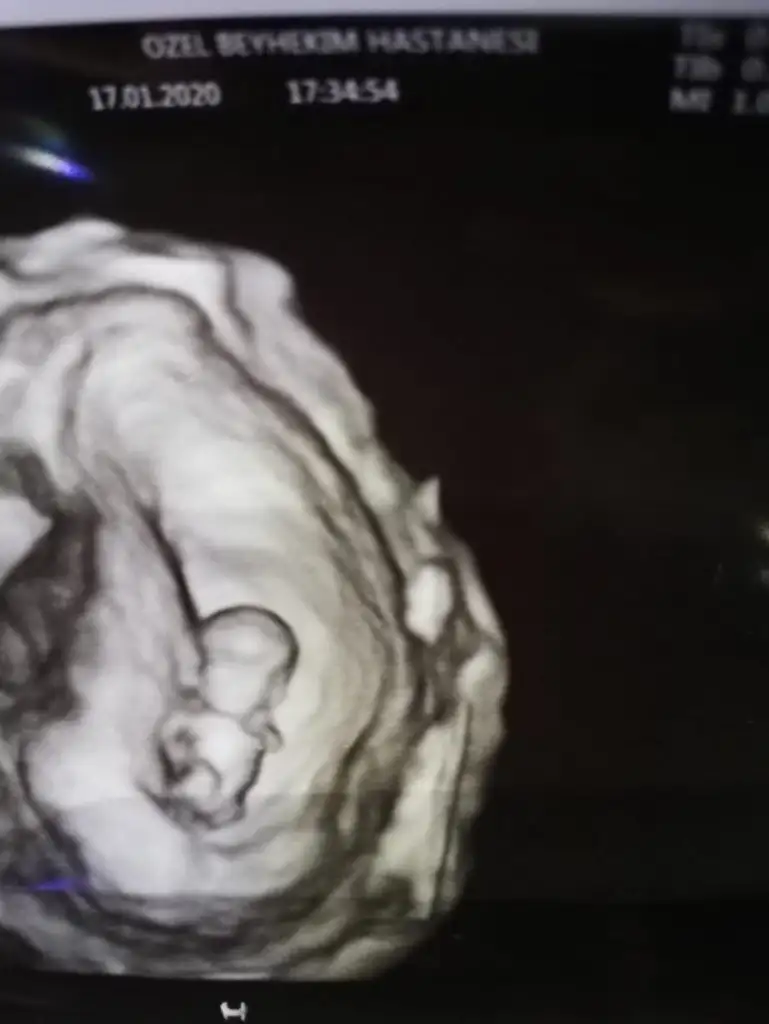

Maşşallah iyi hatırladınNubu paralel kafa yapısı erkek gibi demiştim hayırlısı olsun cnm

Maşşallah iyi hatırladınamin bakalım ama bence kız gbi